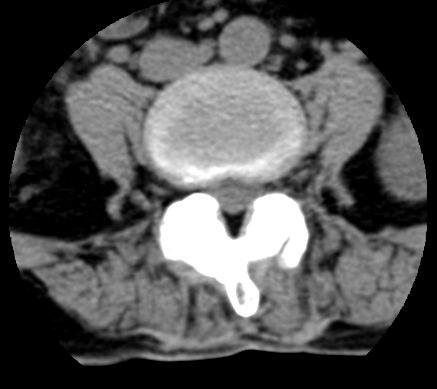

以下是引用余辉在2007-9-4 21:00:00的发言:[br]椎体棘突有点异常(像是被切割了),不知有否手术史,如椎体融合术等。单纯的退行性变可以出现椎间隙变窄,但同时一般会出现椎体上下缘的硬化增生,且椎体间完全融合的机率更小,本例椎体完全融合且椎体上下皮质缘破坏掉了,如果没有手术史,就应该考虑椎间盘炎性病变了,且椎体棘突及棘间韧带的变化也并不是不支持这个,多数小关节也融合了,且其形态也容易让人联想到如强脊炎及类风关等病变。[br][br][本贴已被 余辉 于 2007-9-4 21:03:55 修改过]

以下是引用chry3在2007-9-4 20:42:00的发言:[br]椎间盘病史?是什么样的病史,无双下肢放射痛,那就不是椎间盘突出了。是感染、什么性质的?[br]从图象看椎间隙消失,椎间盘组织未见,锥体滑脱是因为椎间盘溶解造成的[br]l4、5椎体骨质结构未见异常,l5上缘是l4的长期压迫所致[br]还是考虑椎间盘感染,结核。[br]